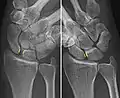

- Static scapholunate dissociation

- Dynamic instability: Increased scapholunate distance (between yellow lines) upon ulnar deviation of the wrist, but not otherwise.